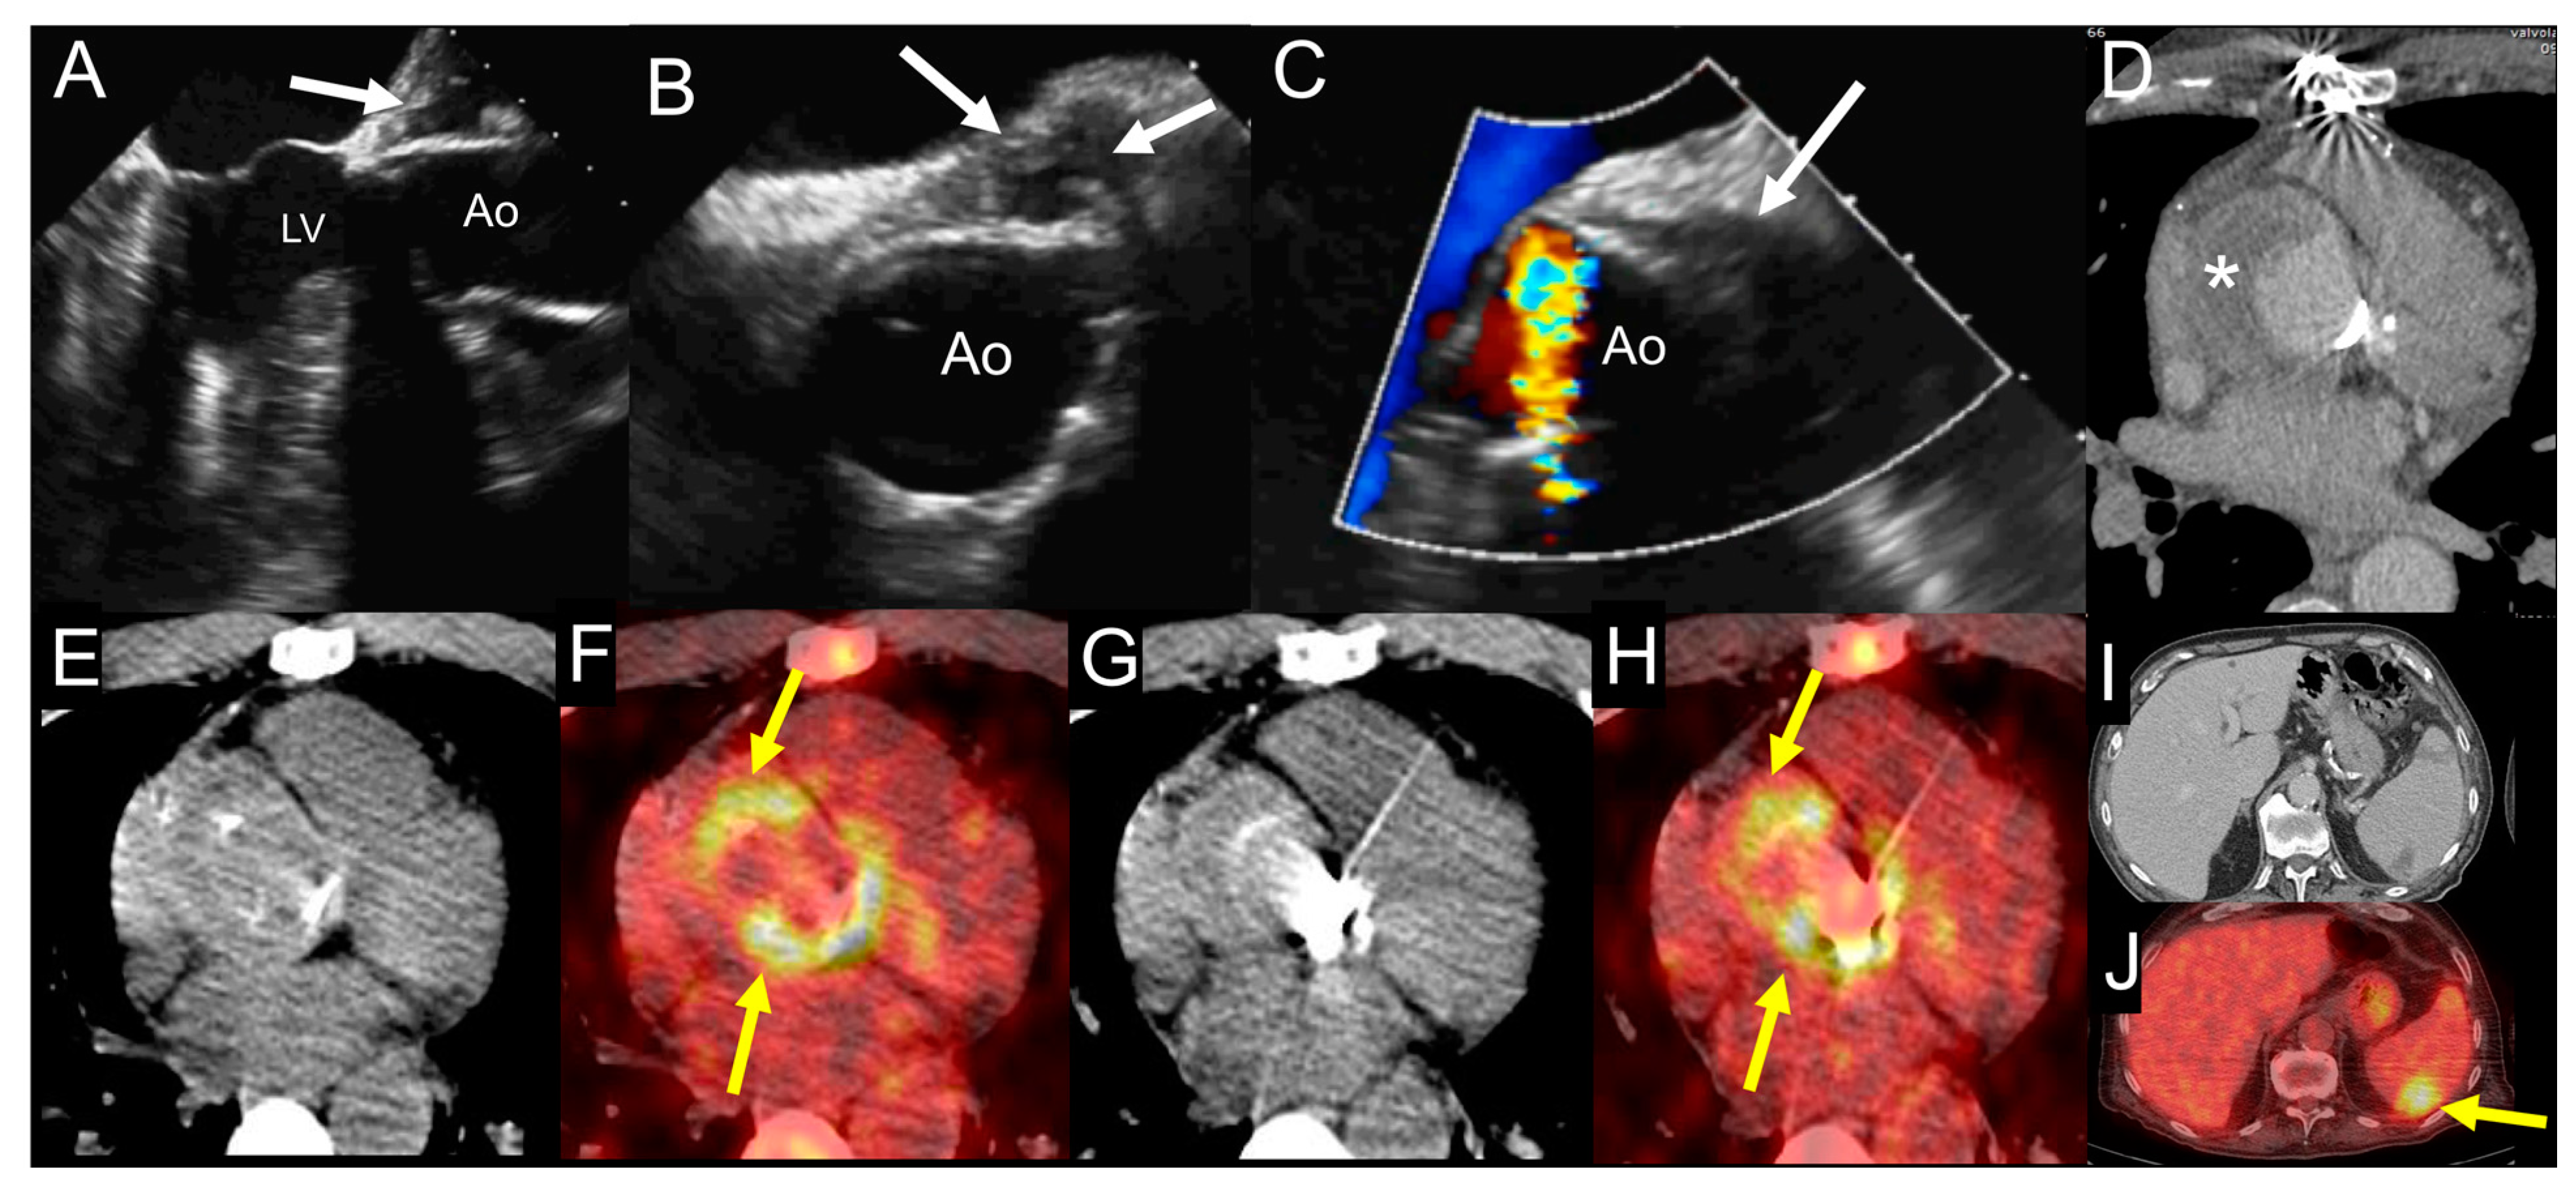

| Left-sided IE | Good visualization of mitral and aortic valve. Valvular dysfuction assessment. Identification of complication (i.e., valvular regurgitation). | Difficult differential diagnosis in presence of marantic vegetations or high calcification. | Detection of vegetations and valve perforation. Assessment of perivalvular extent of disease (abscesses, pseudoaneursysm, fistula). | Inferior to TTE/TOE in detecting small vegetations (<2 mm). | Prognostic assessment: simultaneous detection of embolism, metastatic lesions and portal of entry. | Limited sensitivity for small vegetations. | Evaluation of distant emboli and portal of entry. | Limited role because of low sensitivity for small vegetations. | Capability to assess vegetations (inferior to TTE/TOE). Capability to assess local complications. Independent by acoustic window. May detect concomitant myocardial inflammation. | Not included in current guidelines for IE diagnosis. |

| PVE | Routinely used for follow up; it allows sequential assessment of prosthesis function. TOE is often required to correctly assess the prosthesis. | Limited by prosthetic material artifacts (i.e., acoustic shadow). Early complication (i.e., abscess) can be difficult to identify. | Identification of complications (paravalvular leakage, abscesses, pseudoaneurysm, dehiscence, and extension to adjacent structures). Capability to visualize large vegetations (>10 mm). | Low image quality for beam hardening artifacts. Limited in assessing small vegetations (<4 mm). | High diagnostic accuracy. Good assessment of perivalvular/periprosthetic complications. Reduction of rate of misdiagnosed PVE. Role in prediction of MACEs. Prognostic significance. | Host reaction may reduce specificity (risk of false-positive studies until 3 months after surgery). | High specificity for infection. Reduction of rate of misdiagnosed PVE. Differential diagnosis between septic and sterile vegetations. | Limited sensitivity for small lesions. | Image quality severely hampered by susceptibility artifacts (especially from mechanical prostheses). | |